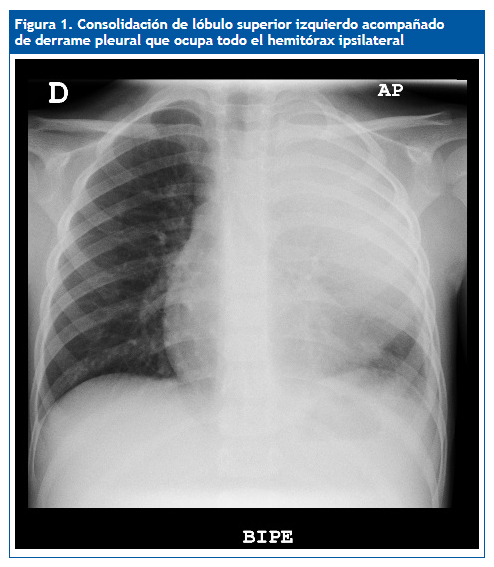

Niño de cuatro años con fiebre de siete días de evolución, diagnosticado de neumonía en el lóbulo superior izquierdo, que ingresa en el hospital con cefotaxima por vía endovenosa; tres días más tarde continua febril y presenta empeoramiento respiratorio con necesidades de oxígeno suplementario. Se realiza una nueva prueba de imagen donde se observa un derrame pleural que ocupa todo el hemitórax izquierdo, alcanzando un espesor máximo de hasta 22 mm (Fig. 1), por lo que se añade clindamicina al tratamiento y se programa drenaje con tubo de tórax. Bioquímica de líquido pleural: parámetros de exudado y antígeno de Streptococcus pneumoniae positivo. Después de diez días recibe el alta a domicilio por su mejoría progresiva, para posterior control en consultas externas.

| Figura 1. Consolidación del lóbulo superior izquierdo acompañado de derrame pleural que ocupa todo el hemitórax ipsilateral |